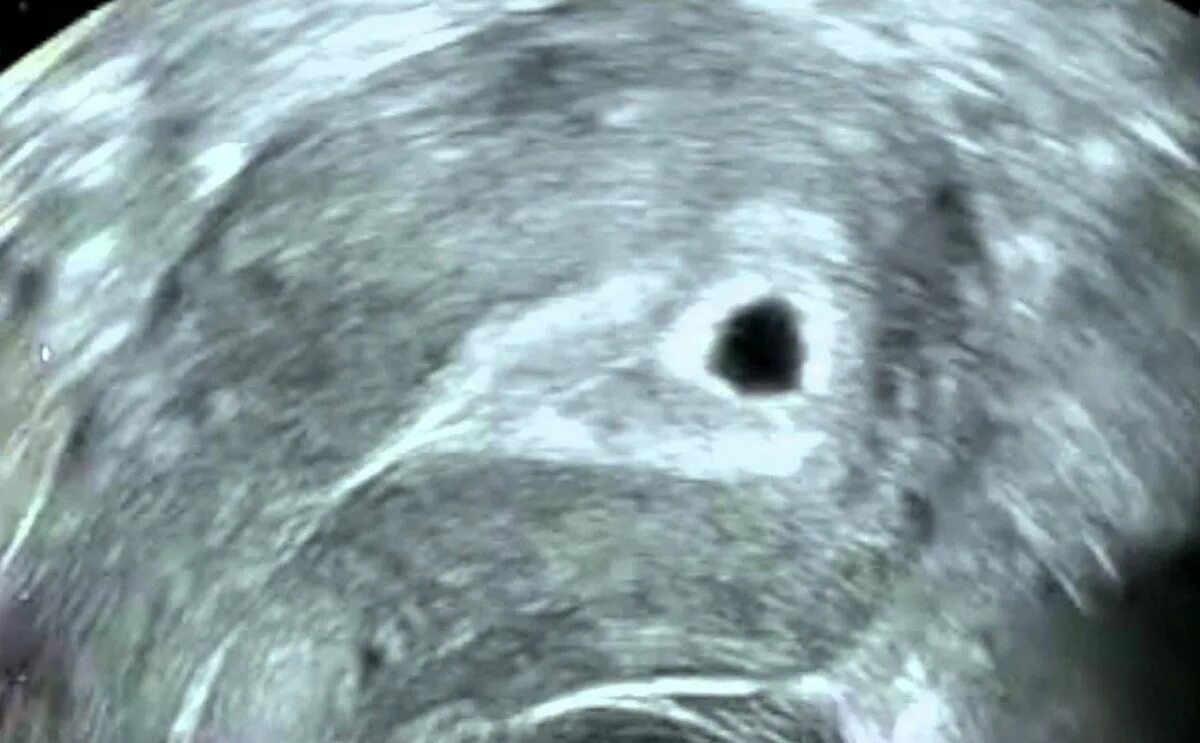

Плодное яйцо 4 5 мм